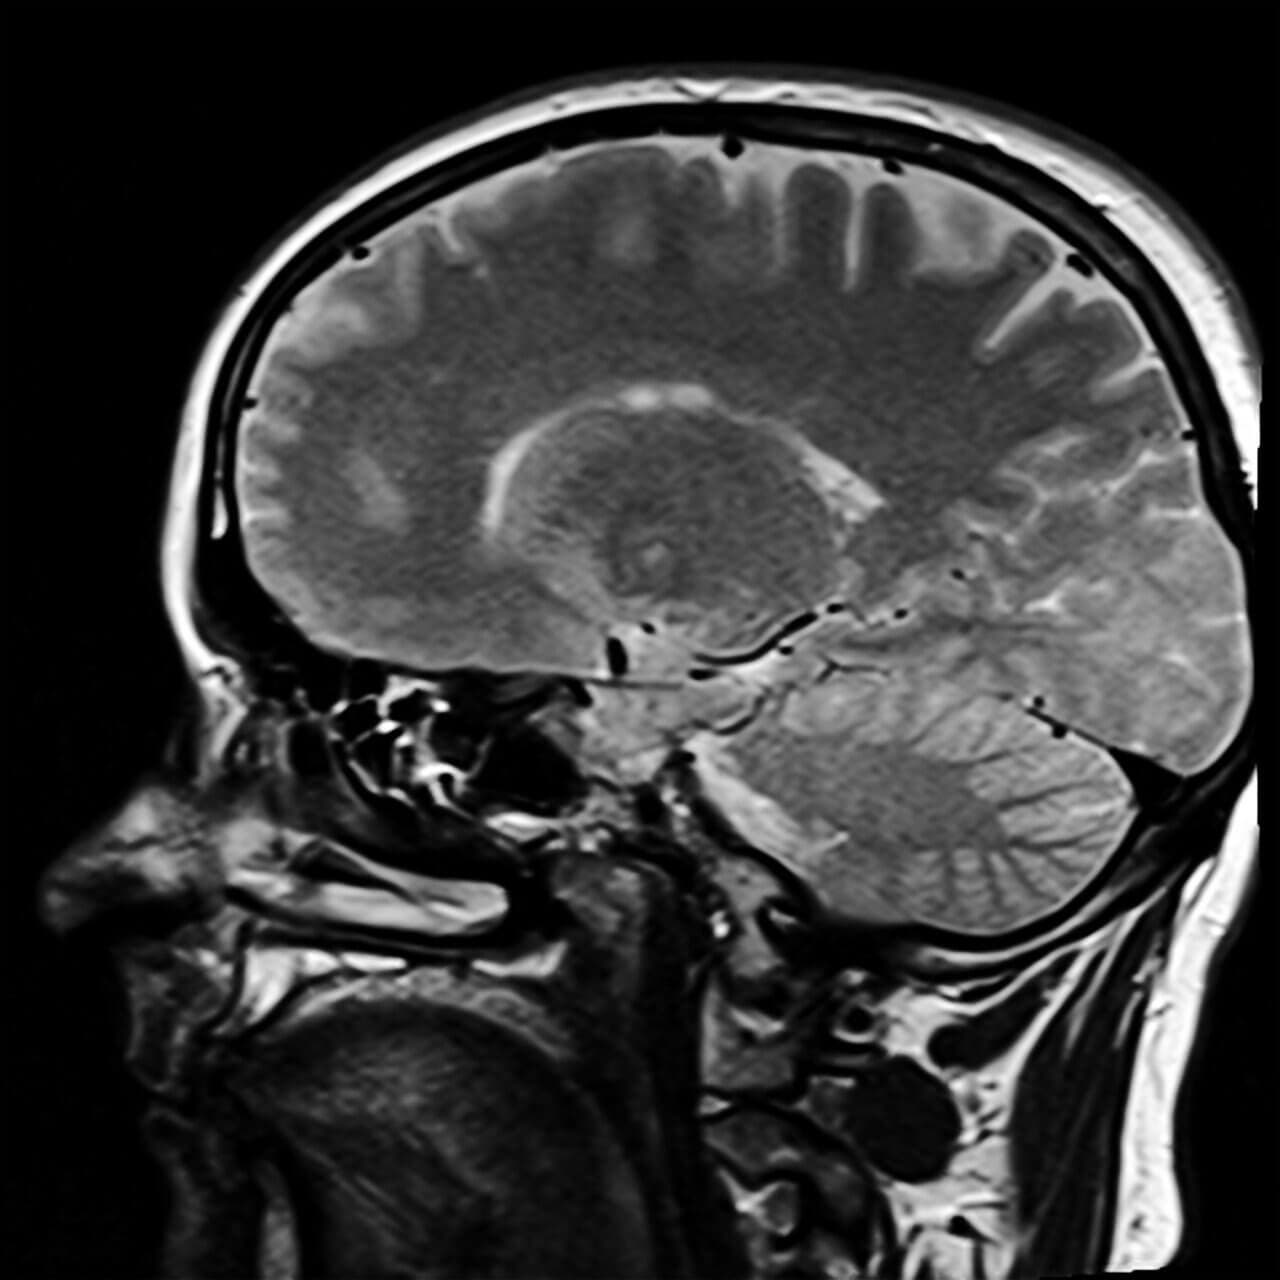

Vi har allerede snakket om hvordan en sosiopat er, men hva skjer i tilfellet av psykopater? I disse situasjonene finner vi mennesker som har forskjellige hjerner.

Noen undersøkelser og studier, som den av Brain Asymmetries in Psychopathy, har vist markante forskjeller i hjernestrukturen til mennesker som har blitt diagnostisert som psykopater.

Det er også problemer i den prefrontale cortex, som gjør hjernen annerledes fra første øyeblikk et menneske blir født. Derfor kan vi si at psykopaten er født; han eller hun trenger ikke å ha en traumatisk barndom, siden det er hjernen deres som har visse egenskaper.